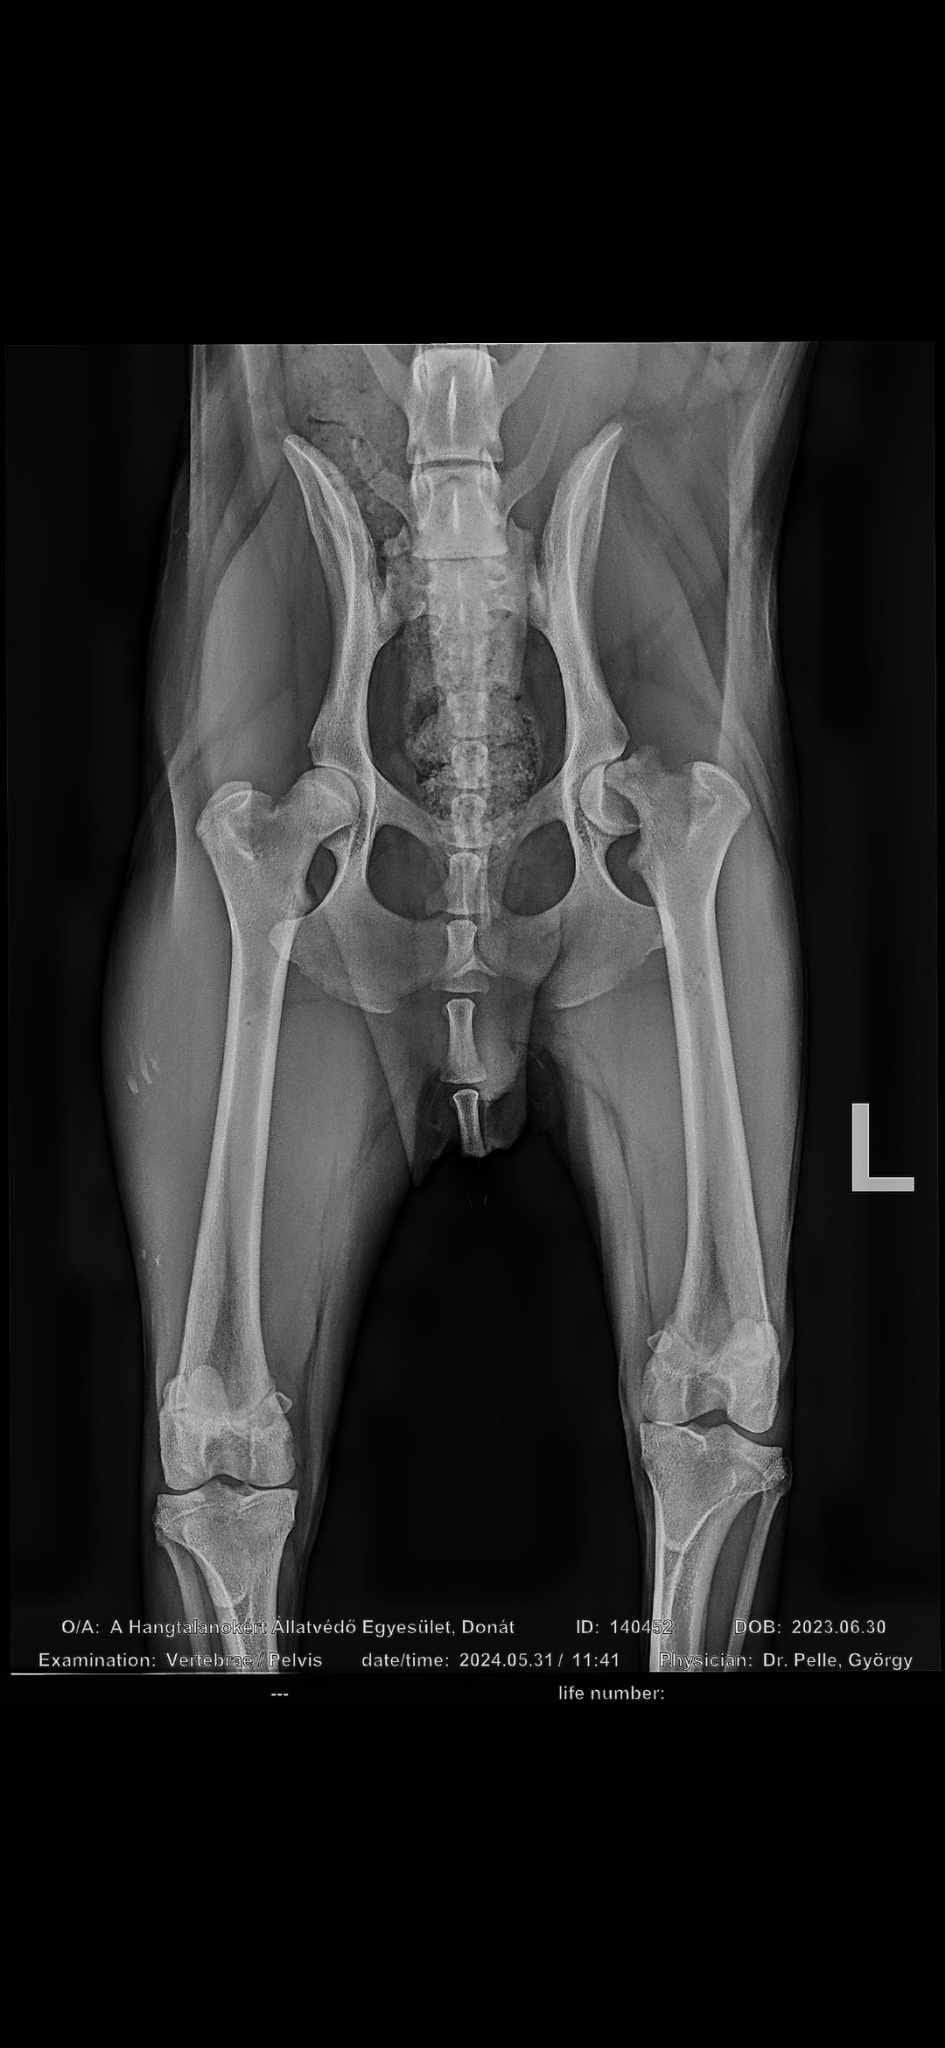

Vor ein paar Tagen stellte unser Partnertierheim feste, dass Junghund Donát hinkt. Nachdem Donát einem Orthopäden vorgestellt und ein Röntgenbild gemacht wurde war leider klar, dass sein Oberschenkelkopf gebrochen ist. Dies ist vermutlich beim springen im Zwinger passiert. Gerade bei jungen Hunden im Wachstum kann so etwas schnell geschehen. Donát wurde am gestrigen Tag operiert und darf Montag wieder zurück ins Tierheim, wenn alles gut geht. Den Eingriff hat Donát Gott sei Dank gut überstanden

. Auf Donát wird eine schwierige Zeit zukommen, er muss ruhig gehalten werden, damit alles vollständig und gut heilen kann. ![]()